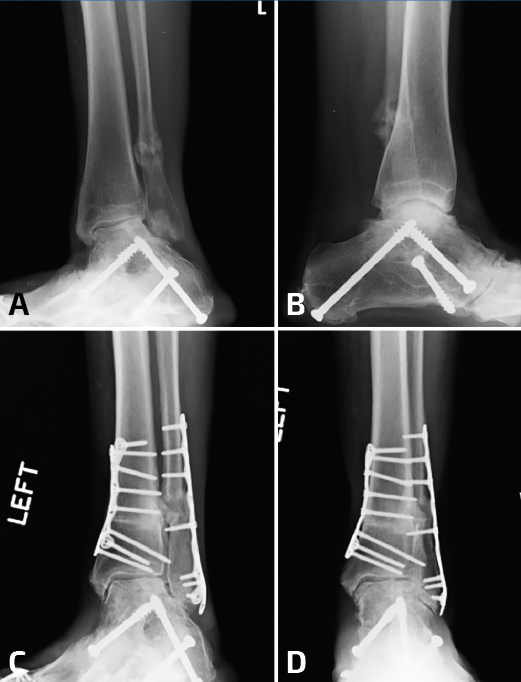

Durante la reconstrucción de la pseudoartrosis, es esencial realizar una artrotomía anterolateral para visualizar la reducción anatómica del peroné (Figura 1); sin embargo, el desbridamiento artroscópico de la articulación debe realizarse en forma simultánea no tanto para determinar el grado de artritis del tobillo, sino para tratar alguna lesión osteocondral no visible con la artrotomía anterolateral.

Figura 1. Cuando es necesaria una elongación significativa, se debe desbridar toda la sindesmosis anterior y dejar libre el peroné. Es indispensable para este paso un separador de láminas.

El tejido hipertrófico entre el maléolo interno y el astrágalo debe resecarse desde el receso interno para el correcto reposicionamiento del astrágalo. Esto se puede lograr por vía artroscópica o mediante una artrotomía anteromedial. Esto es importante tenerlo en cuenta, ya que una pequeña cantidad de tejido en la gotera interna puede bloquear el correcto desplazamiento medial del astrágalo dentro de la mortaja. La pseudoartrosis del peroné por lo general se asocia con un desplazamiento lateral del astrágalo, con un aumento del espacio claro medial, motivo por el cual se debe limpiar toda la gotera interna (Figura 2).

Figura 2. Aquí mostramos la técnica de elongación. Después del desbridamiento de la sindesmosis, se coloca la placa sobre el peroné y de colocan 2 o 3 tornillos distales (A, B). Se coloca un tornillo de 3,5 en el peroné proximal a la placa y el separador de láminas entre el tornillo y el borde proximal de la placa (C, D). En este caso, para corregir la consolidación viciosa del maléolo medial, se realizó una osteotomía (E) y el control de radioscopia intraoperatorio muestra una buena reducción de la sindesmosis (F).